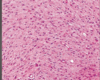

Describe what you see here; what condition is this

rounded atrophic fibers and lymphocytic infiltrate; top right is macrophages attacking muscle fiber; polymyositis